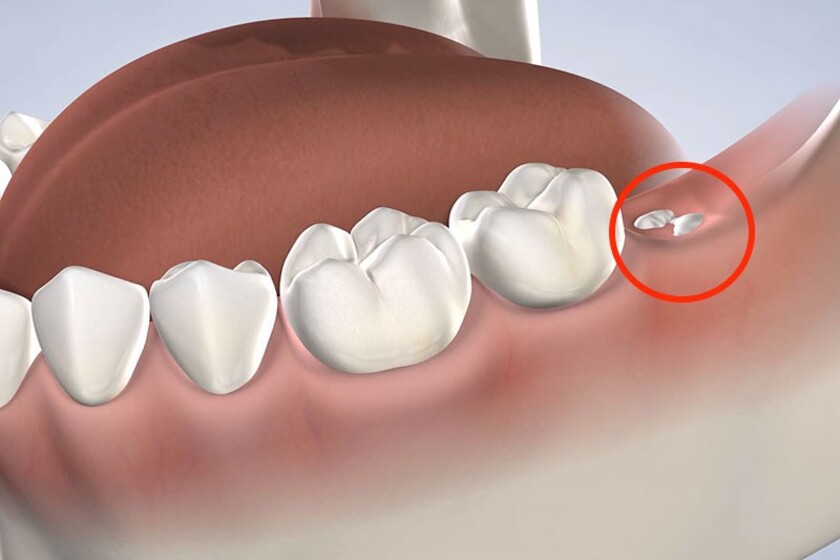

Mọc răng khôn

Đây là tình trạng khá phổ biến ở lứa tuổi trưởng thành khi răng khôn mọc ngầm, mọc lệch gây đau nhức và ảnh hưởng đến các răng bên cạnh. Răng khôn hay răng số 8 là chiếc răng cuối cùng mọc trên cung hàm. Do không đủ chỗ trong cung hàm cho những chiếc răng này mọc nên chúng thường mọc ngầm hoặc không đúng vị trí. Chúng gây ra tình trạng đau âm ỉ kéo dài và lặp đi lặp lại nhiều lần. Răng khôn mọc còn khiến nướu bị sưng tấy, ăn uống khó khăn. Đôi khi còn gây sốt, chán ăn, ảnh hưởng nghiêm trọng đến sinh hoạt hàng ngày.

Cách trị đau răng do mọc răng khôn

Bệnh nhân nên được chụp phim để biết răng khôn mọc thẳng hay lệch. Bác sĩ có thể kê đơn thuốc giảm đau và thuốc kháng sinh để giảm viêm mô mềm và ngăn ngừa tổn thương nghiêm trọng cho các răng khác. Trường hợp răng mọc ngầm, mọc lệch cần được nhổ bỏ để tránh đau nhức và ảnh hưởng đến các răng khác.

Nhổ răng khôn mọc lệch giúp tránh đau nhức và ảnh hưởng đến các răng khác